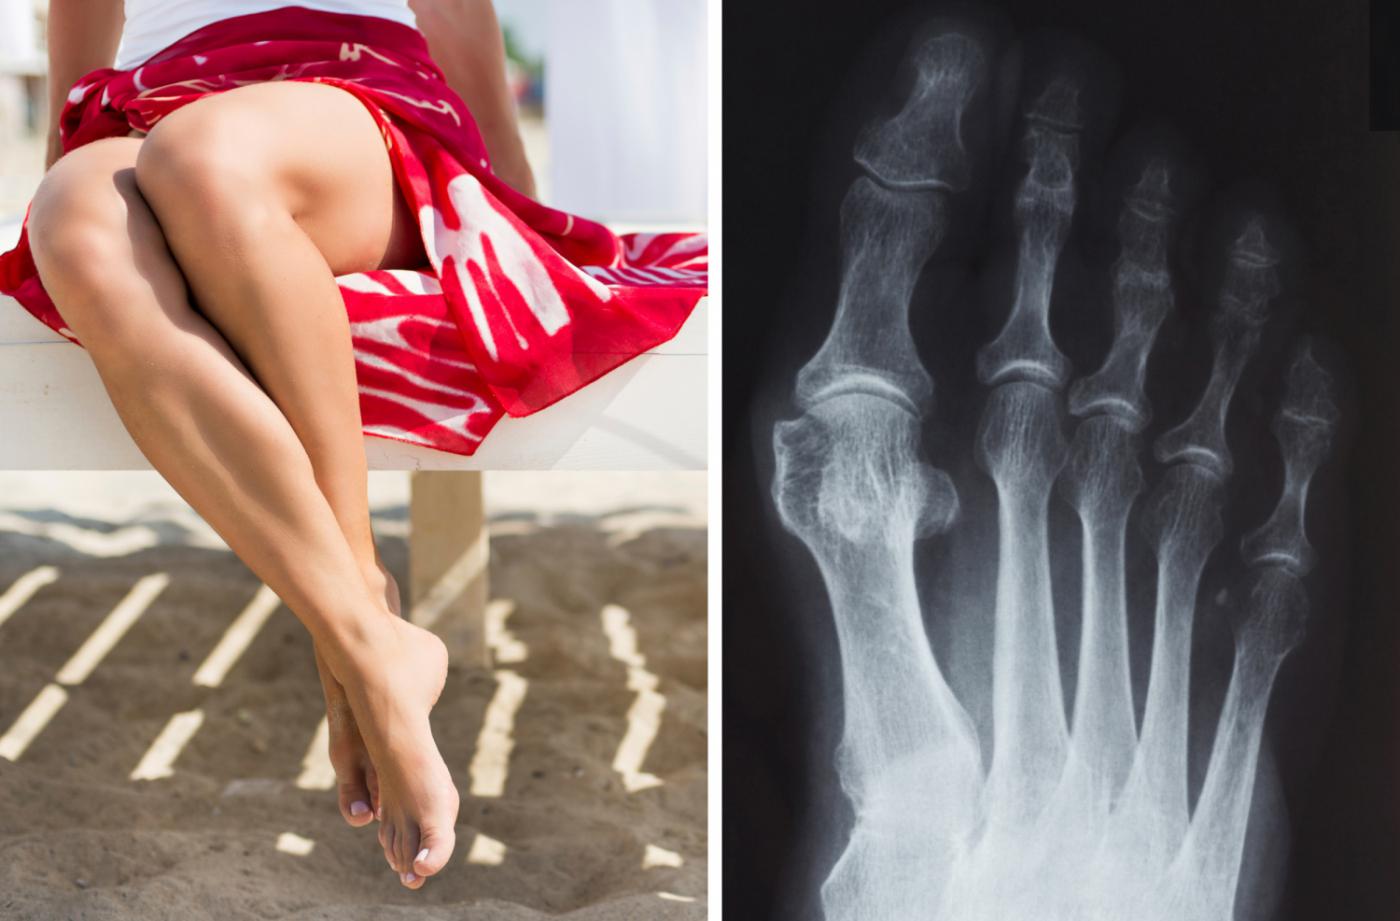

То, что в обиходе мы называем косточкой на большом пальце ноги, на научном языке звучит как вальгусная деформация пальца стопы. Никакой «шишки» на ноге нет. Это только так кажется. На самом деле – это отклонение первой плюсневой кости стопы во внутреннюю сторону с одновременным наклонением большого пальца к наружней стороне. Если на проблему сразу не обратить внимание, то ситуация со временем только ухудшится. Постепенно косточка будет все сильнее выпирать. Это не только уродует ногу, но и причиняет сильную боль при ходьбе. А кроме того создает невероятные трудности при выборе обуви.

Бывает, что косточку на большом пальце ноги принимают за артроз, подагру или отложение солей. Поставить диагноз может только врач-ортопед на основании визуального осмотра и рентгена стоп, а также анализа крови.

Если же стопа уже расплющена, стала шире, а мы все по-прежнему ходим в тесной узкой обуви, то происходит следующее. Первая плюсневая кость постепенно отклоняется от своего правильного положения. Смещение пальца и этой кости ведет к образованию так называемого вальгусного угла. Головка плюсневой кости является его вершиной, которая со временем утолщается и преобразуется в ту самую косточку, которую не скроешь.